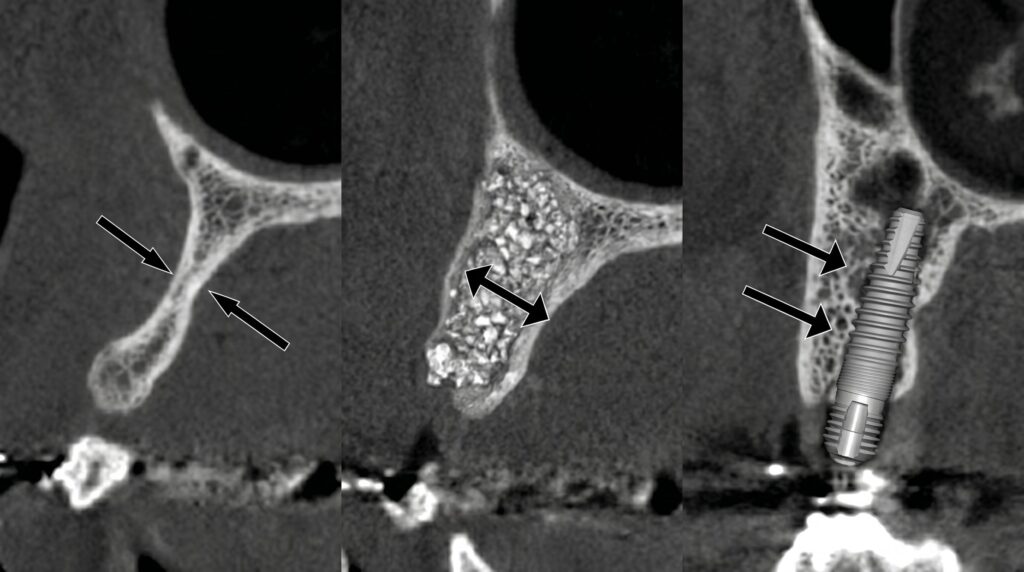

상악동 거상술은 위턱 어금니 부위에 특화된 술식입니다. 위턱 어금니 바로 위에는 코 안쪽의 공기 공간인 ‘상악동’이 위치하고 있어, 발치 후 시간이 지나면 상악동이 아래로 내려오면서 임플란트를 심을 공간이 부족해집니다. 이때 상악동 바닥을 안전하게 들어올린 뒤 그 공간에 뼈이식재를 충전하는 것이 상악동 거상술입니다. 접근 방식에 따라 외측 접근법(창문형)과 내측 접근법(오스테오톰)으로 나뉘며, 잔존 골 높이에 따라 술식을 선택합니다. 고난이도 케이스일수록 집도 경험이 중요한 수술입니다.